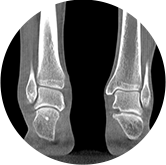

支持雙腿或雙側髖關節掃描 | 方便對比,降低漏診誤診

FOV 250mm

FOV 350mm